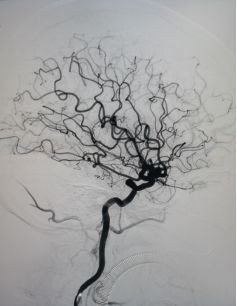

影像学检查:

入院后行DSA检查明确右侧颈内动脉眼动脉后下方囊状动脉瘤样影,大小约1.09mm×6.53mm,宽基底,其下方见两个小囊状突起,左侧颈内动脉眼动脉后方及虹吸段均可见小囊状突起。考虑颅内多发动脉瘤。